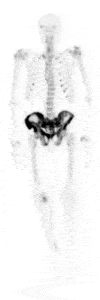

Scanare osoasă 3D

Detectorii digitali care captează un număr maxim de fotoni oferă imagini 3D detaliate, superioare tehnologiei planare Anger. Sistemul SPECT/CT multifuncțional permite scanări complete cap–picioare într-o singură sesiune, oferind informații precise și reducând disconfortul pacientului.

- Workflow-ul SPECT/CT total-body cu acoperire continuă de 2 m oferă eficiență superioară și informații detaliate față de scanările planare tradiționale. Imaginile 3D corectate pentru dispersie, atenuare și volum parțial pot genera, la nevoie, vizualizări multi-view planare (MVP).